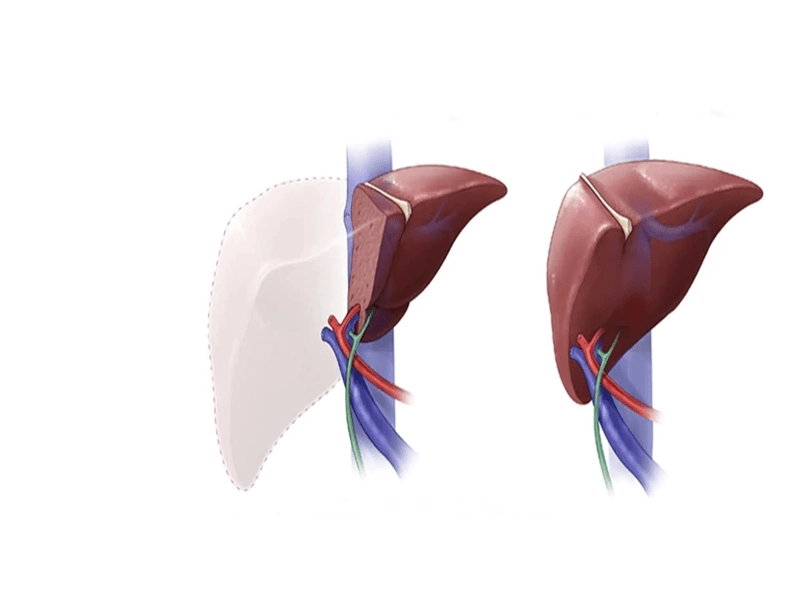

جراحی هپاتوبیلیاری به مجموعهای از روشهای جراحی گفته میشود که برای درمان بیماریها و اختلالات مربوط به سیستم هپاتوبیلیاری انجام میگیرد. این جراحیها میتوانند شامل برداشتن تومورها، ترمیم آسیبها، باز کردن انسدادها و یا پیوند اعضا باشند. به دلیل پیچیدگی و حساسیت این اندامها، جراحیهای هپاتوبیلیاری معمولاً توسط جراحان متخصص و با تجربه انجام میشود.

- سرطان: سرطان کبد، کیسه صفرا، مجاری صفراوی یا پانکراس ممکن است نیاز به جراحی داشته باشد.

جراحیهای هپاتوبیلیاری نقش مهمی در درمان بیماریها و اختلالات مربوط به کبد، کیسه صفرا، مجاری صفراوی و پانکراس دارند. اگرچه این جراحیها با خطراتی همراه هستند، اما میتوانند به بهبود کیفیت زندگی و حتی نجات جان بیماران کمک کنند. با پیشرفت تکنولوژی و روشهای جراحی، میزان موفقیت و ایمنی این جراحیها به طور قابل توجهی افزایش یافته است. با این حال، تصمیمگیری در مورد انجام جراحی هپاتوبیلیاری باید با مشورت پزشک و با در نظر گرفتن تمام جوانب صورت گیرد.